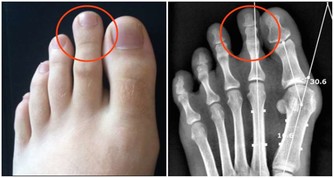

要知道我們是否缺維生素或者微量元素,要看身體出現哪些不正常表現。